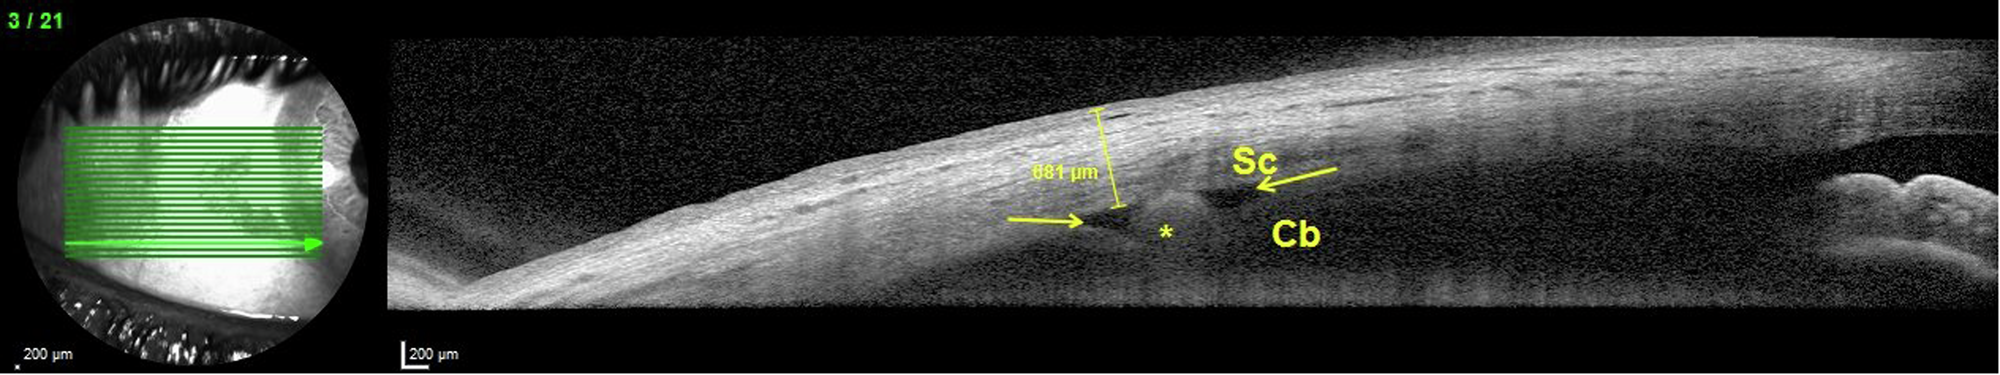

Fig. 3: Anterior segment optical coherence tomography of a patient with suprachoroidal DEX implantation in the postoperative first week.

The anterior segment optical coherence tomography shows the implant (yellow asterisks). The image demonstrates that the suprachoroidal space, previously a potential space, has become visible due to implantation, indicated by yellow arrows. Cb ciliary body, Sc sclera.